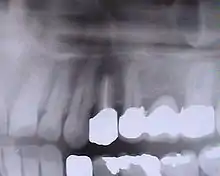

Bridge ou pont dentaire

Le bridge (ou pont dentaire au Québec[3]) répond aux mêmes critères esthétiques et d'occlusion. La prudence est de mettre en place autant d'implants que de dents à remplacer. C'est moins vrai à la mandibule faite d'un os plus compact qu'au maxillaire supérieur fait d'un os spongieux.

Bridge en place, la gencive n'est pas visible lors du sourire.

Bridge sur modèle en plâtre.